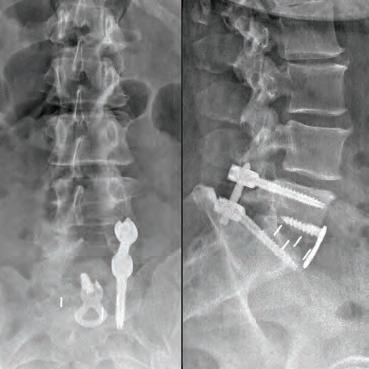

Her neck fusion required a 24-hour hospital stay and a six-week recovery period, before her back surgery. While the neck fusion alleviated the numbness and lack of strength in her hand and arm, her back surgery was becoming increasingly more urgent as she was losing the ability to use her right leg and walk. “My right leg under my knee felt too heavy to pick up when I tried to walk,” explained Cheryl.

When it came time to address her back, Dr. Arakal re-evaluated her completely and determined that while he could do a fusion on her back that wasn’t what she needed. “‘What you need,’ he said, ‘is an ultra-minimally invasive discectomy which is done endoscopically so that it doesn’t disrupt your tissue but more importantly so that it doesn’t disrupt your bone,’” details Cheryl. In this ultra-minimally invasive spine surgery, relief is generally immediate and it requires a very small incision.

Armed with this information, Dr. Arakal referred Cheryl to Dr. Peter Derman a fellow orthopedic spine surgeon at Texas Back Institute who specializes in this specific procedure.

Sending her to Dr. Derman further bolstered Cheryl’s confidence in Texas Back Institute. “They will refer you to the proper doctor for your

specific needs and they will ensure the right surgery for you. I’ve always known that, but as I was going through the process, it struck home in a different way,” she says. “Why would you go anywhere else? You would want to go to a place where you know no matter what’s wrong with you, you’ll end up with the surgeon right for you.”

“One of the things I was most impressed by was that the doctors were very thorough in explaining to me exactly what was going on with my body during this process. They make sure their patients know what’s happening, what they’re going to do, why they’re going to do it, and what the results should be,” Cheryl explained. Six weeks after her neck fusion, Cheryl went in for back surgery at 1 p.m. and was home by 5:30 p.m. the same day. “I’m an insider and work for these doctors, I get it, but when it happens to you, it’s weird. I had just gotten back from recovery, and they said, ‘You’re going home.’ I thought, ‘I can’t walk, I just got back from recovery,’” says Cheryl, who was pleasantly surprised to find out she could walk without any issues.